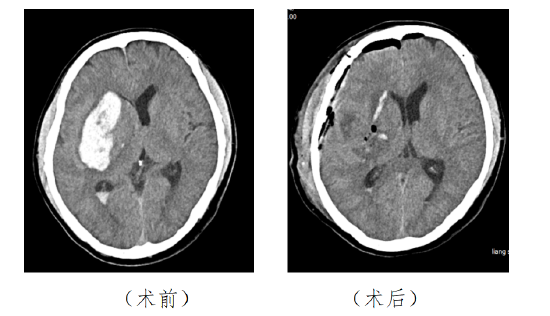

“患者接受颅脑CT检查后显示基底节区出血,后以‘高血压脑出血’转至我科进一步治疗。”海医二院神经外科一区冯基高主任医师介绍说。

然而,入院后患者病情仍不稳定,接下来出现意识不清的症状,经过紧急复查CT,发现其基底节区脑出血增多,冯基高决定对其实施开颅血肿清除术。术后患者被转入重症监护室继续接受监护治疗及抗感染、降低颅内压等治疗,至两周后意识逐渐恢复,精神状态转好,顺利康复出院。